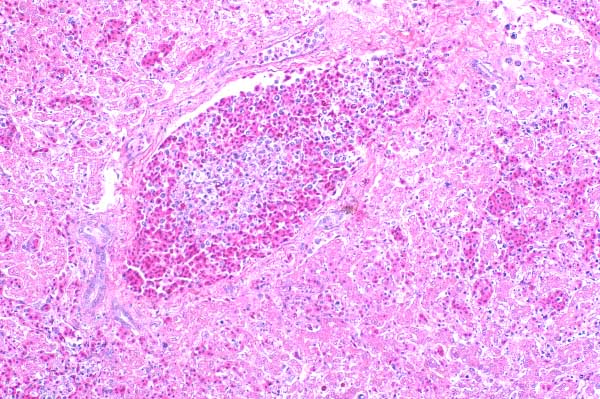

| 10x   |   Hematoxylin and Eosin | ||||

Blood vessels are congested, and their walls are disrupted by karyorrhectic debris, fibrin, erythrocytes and inflammatory cells.